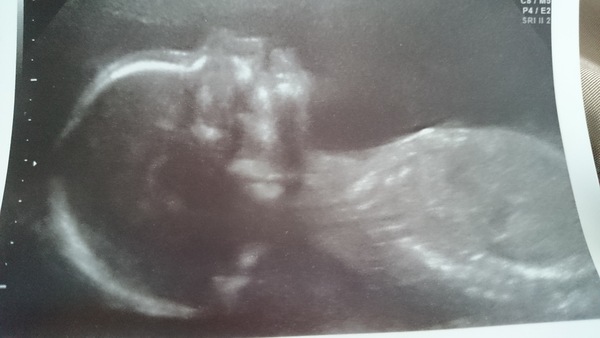

I've been lurking again for while but been.quite nervous about scan this time round so haven't been posting. Glad to see others good news (and not so good tooth news) had my scan today and all well thankfully so feeling good bit more relaxed. Though back in 4 week for uterine artery scan. Got some slightly fuzzy pics of no 2

Congrats on scan news Nyan! That's a really clear pic!! So cute! Team pink/blue/yellow? :)

Great pic Nyan Smile